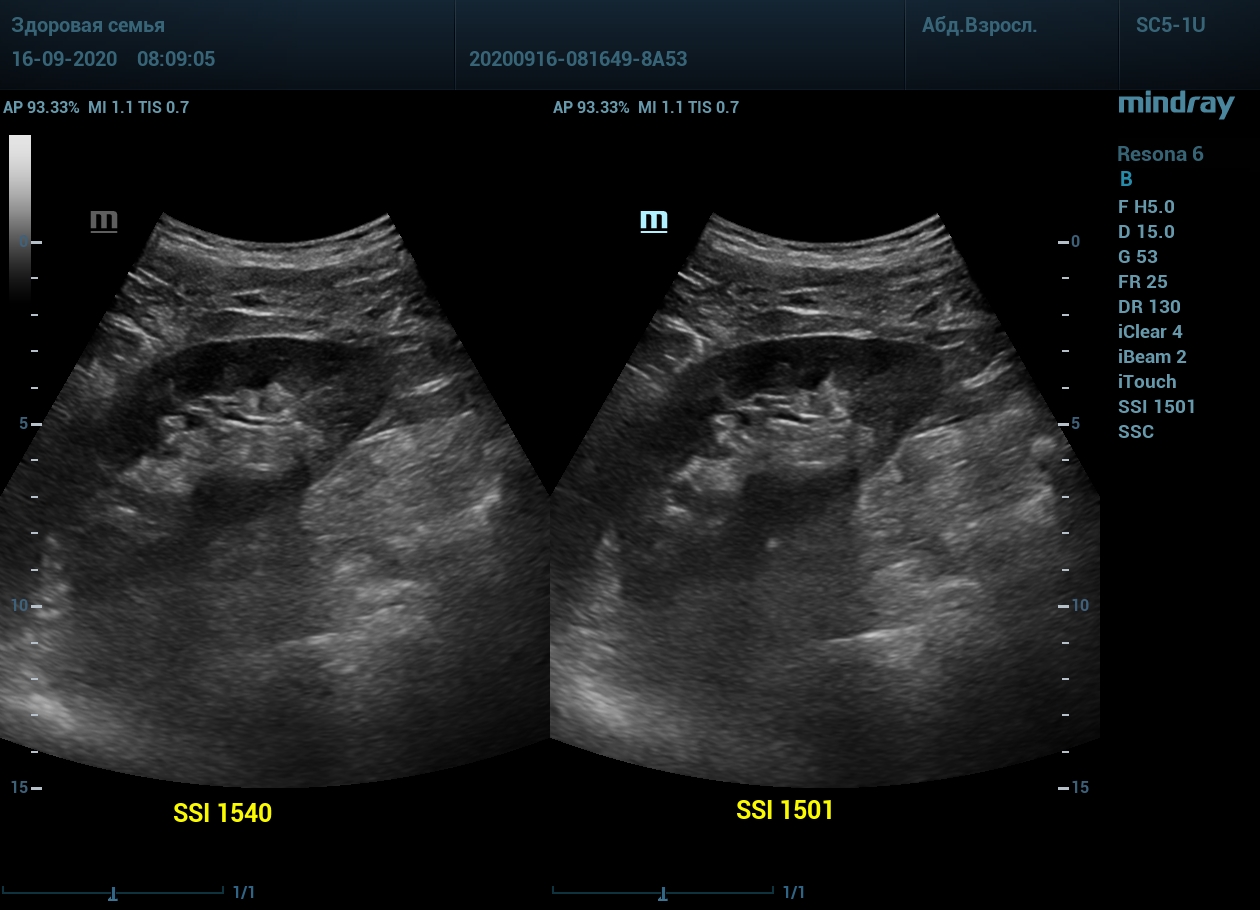

1. Пациент с метеоризмом и большой массой тела. Визуализация поджелудочной железы до и после калибровки скорости ультразвука. Контуры головы и тела железы видны гораздо лучше.